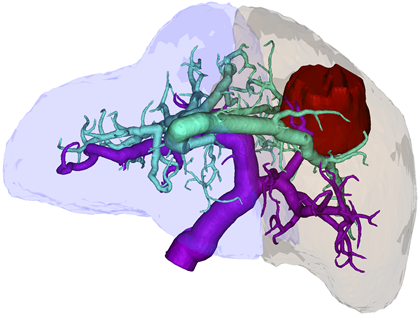

(Manual) Vessel Segmentation

We are looking for a student assistant („Hiwi„) for carrying out vessel segmentation in tomographic image data. After the segmentation, a transformation into 3D surface models should be carried out, including postprocessing of the surface meshes.

Vessel Tree Analysis

We want to develop an automatical vessel tree analysis tool for medical vascular structures. This is important for tumor surgery planning (which vessel should be spared? which vessel is at risk by the tumor location? …) but also for stroke analysis (which vessel supporting the brain might be hampered?).